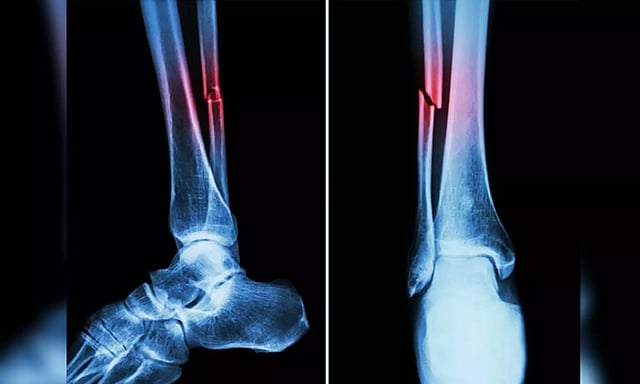

In the study, mice who had Covid-19 showed significant bone loss. This loss decreased the bone mechanical strength and increased the risk of fractures.

If similar bone loss occurs in human patients following their Covid‐19 recovery, it could leave them with a long‐term -- even permanent -- increased risk of fractures due to fragile bones. This is especially true in elderly patients.

The study suggested that the higher risk of fragility fractures, when a person falls from standing height or less, may be one of the underreported long-haul symptoms of Covid.